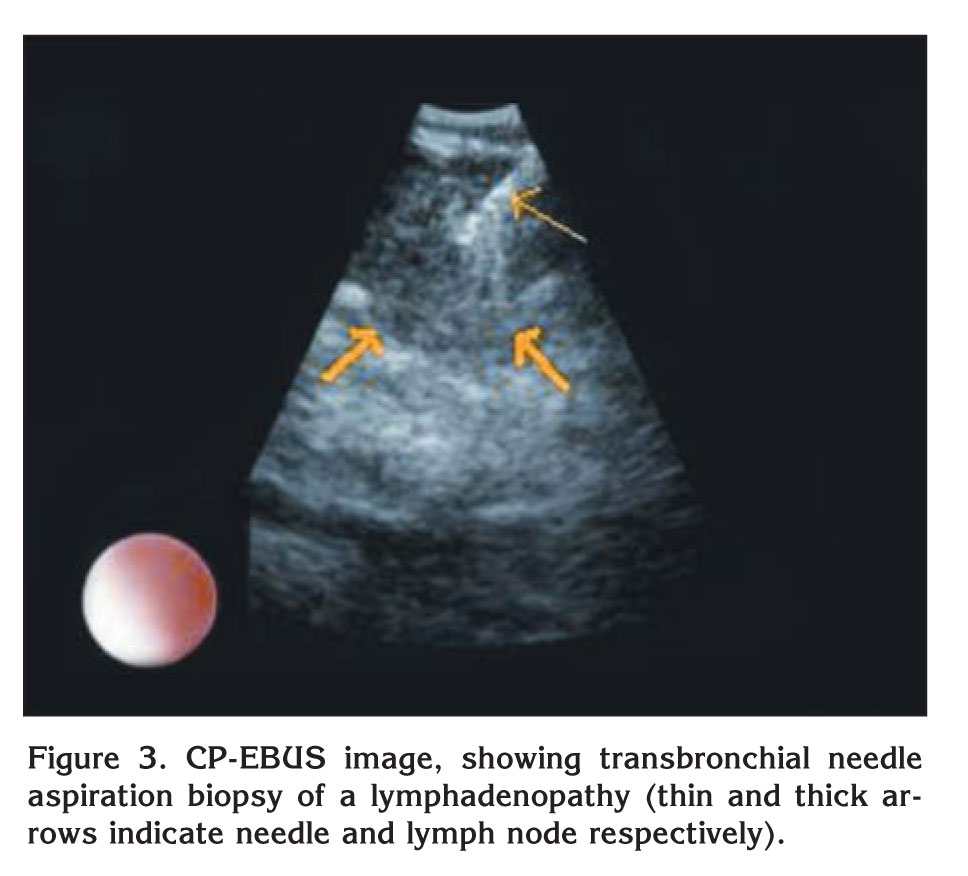

A 63-year-old male patient presented with acute dyspnea and pain in his right chest. Chest radiography revealed fullness in the right hilar region. Arterial blood gase sampling revealed respiratory alkalosis and hypoxemia. Plasma D-dimer level (quantitative) was high (5.12 mg/L). Bedside echocardiography revealed enlarged right cardiac chambers, left ventricle hyperthrophy; diastolic dysfunction in the left ventricle, severe pulmonary hypertension. Systolic pulmonary arterial pressure was 110 mmHg. The patient was suspected of having pulmonary thromboembolism and was evaluated by contrast-enhanced, computed tomography-angiography of the chest (angio-CT). In the evaluation, the following findings were determined: a hypodense lesion of approximately 3 cm in diameter that was limited to a lobule in the right hilus; multiple lymphadenopathy, the largest of which was 23 mm in diameter, in the right lower paratracheal and subcarinal locations, and a thrombus that was 18 mm thick and adherent to the anterior wall in the right main pulmonary artery. The border between the thrombus and the soft tissue of the right hilar could not be discriminated (Figure 1). After ten days of low molecular weight heparine treatment, patient became hemodynamically stable. Arterial blood gas (collected in room temperature) analysis after the treatment was pH: 7.40, PaCO2: 39.2, PaO2: 67 and oxygen saturation: 94%. After that, to obtain diagnostic samples from the lymphoadenopathies and to evaluate the relationship between the soft tissue of the right hilar and the right pulmonary artery, we performed convex probe (CP) endobronchial ultrasound (EBUS). Pulmonary arteries (PA) were echo free. On the image of the embolus in the right PA, an echogenic mass that was surrounded by blood flow and floating within the wall was visualized. The blood flow surrounding the embolus was easily seen by the power doppler mode of the EBUS bronchoscope (model BF 240, EU-ME1 Olympus, Tokyo, Japan) (Figure 2). There was also a heterogenous lymph node with irregular borders. However, the border between this lymph node and the right pulmonary artery was definite. In addition, a homogenous, vascular, lobulated lymphadenopathy with regular contours in the subcranial area and a heterogenous, irregularly contoured lesion extending from the right lower paratracheal area to the upper paratracheal area were detected. Histopathological evaluation of the fine needle aspiration from the subcranial lymphadenopathy and the lesion showed adenocarcinoma (Figure 3).

Figure 3